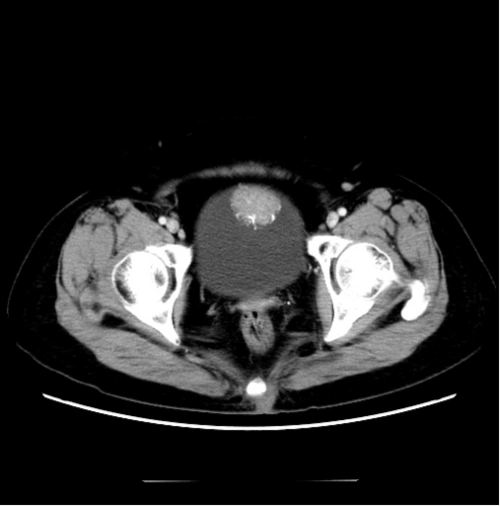

1.2o19年3月全腹平扫 增强ct,膀胱部分片3

【病例】膀胱癌1例ct影像表现

术前ct见膀胱左侧壁占位.

1月20日增强ctu ,膀胱部分片2